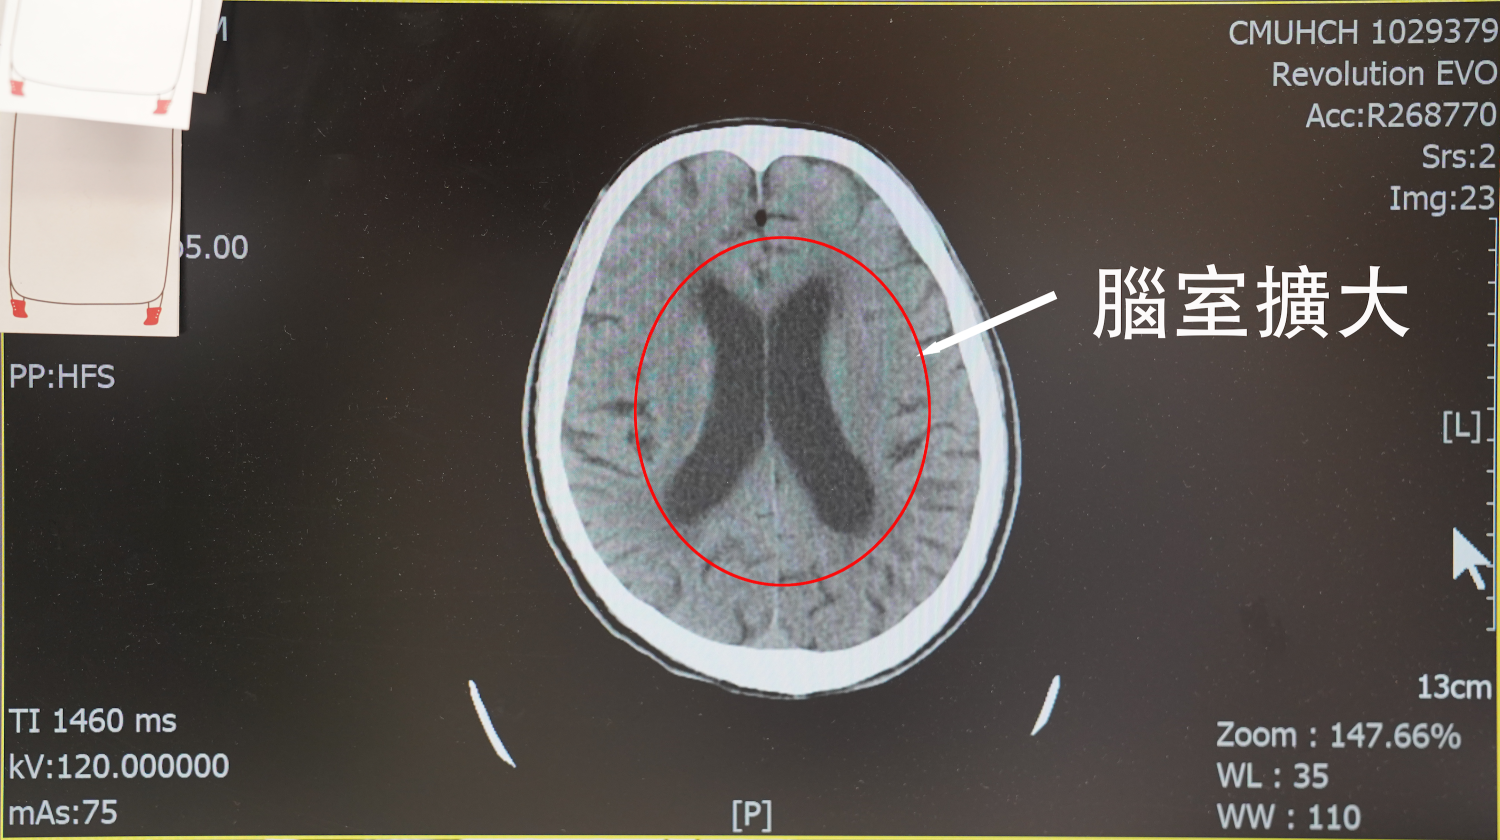

一名73歲王姓病患因全身無力、走路不穩、胡言亂語等症狀,前往中國醫藥大學新竹附設醫院神經內科求診,經錢駿醫師診斷後發現,患者還伴有輕微癡呆與尿失禁,進一步安排電腦斷層檢查,確認為常壓性水腦症。此病因腦脊髓液蓄積導致腦室擴大,壓迫腦部組織,引發多種神經學症狀。